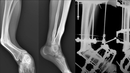

Врачи Центра Илизарова помогли жительнице Приморского края исправить деформированную стопу. По словам специалистов, это уникальный случай с большим сроком давности травмы.